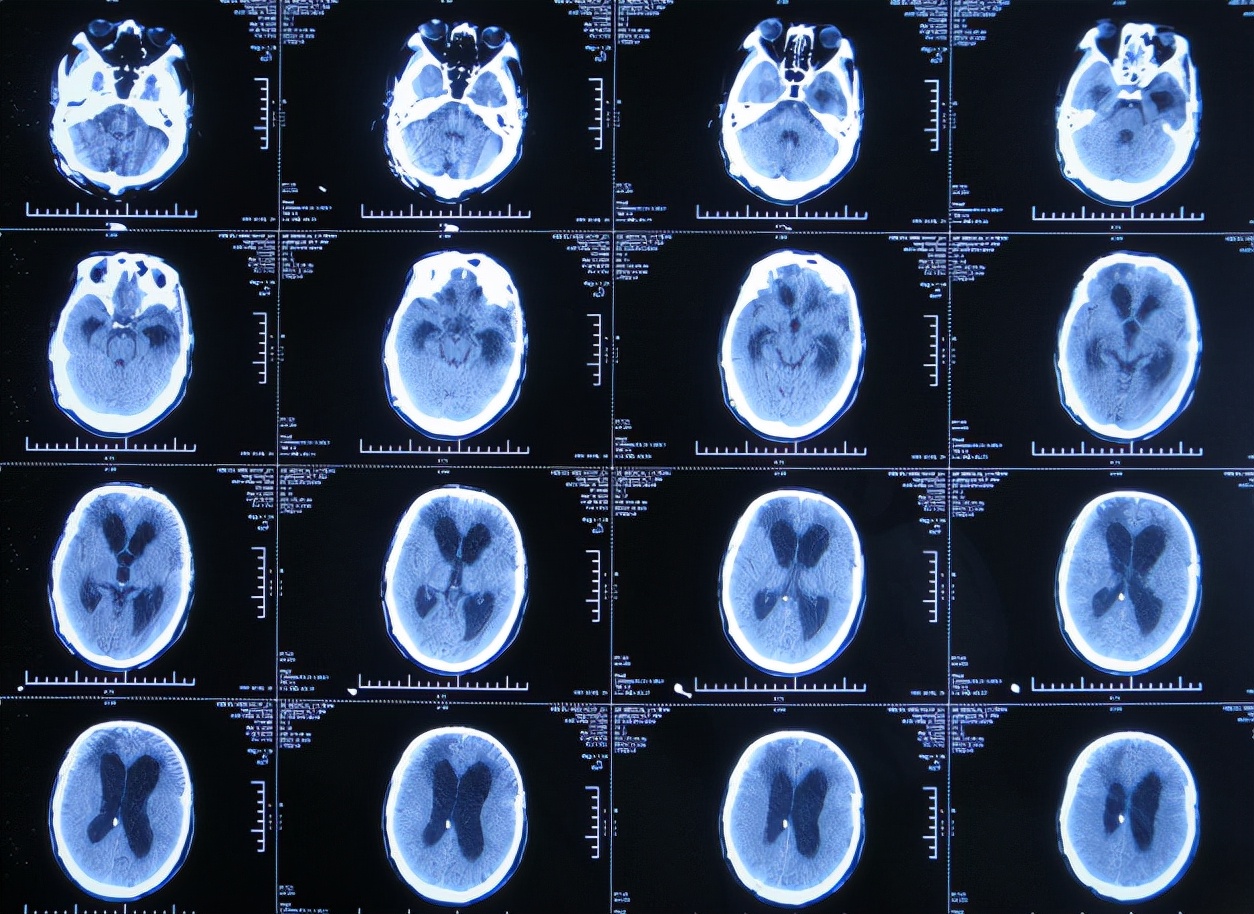

入院3天即2019年12月13日,同时进行了颅骨修补术+脑室腹腔分流术。术后3天即2019年12月16日,在搀扶下可以下床走路活动,查头颅CT示颅骨修补术后+脑室引流术后状态( 图-15 )。

图-15: 2019年12月16日头颅CT

但颅骨修补术+脑室腹腔分流术后第5天即2019年12月18日,出现意识有点不清。

颅骨修补术+脑室腹腔分流术后第6天即2019年12月19日,复查头颅CT示引流管周围少量出血( 图-16 ),给予拔除头部引流,换做腰大池引流。

图-16: 2019年12月19日头颅CT

腰大池引流术后5天即2019年12月24日(颅骨修补术后11天即拔除脑室引流管后5天),查头颅CT示脑室仍扩张( 图-17 )。

图-17: 2019年12月24日头颅CT

腰大池引流术后8天即2019年12月27日(颅骨修补术后11天即拔除脑室引流管后8天),查头颅CT示脑室有缩小,积血减少( 图-18 )。

图-18: 2019年12月27日头颅CT

腰大池引流术后11天即2019年12月30日(颅骨修补术后11天即拔除脑室引流管后11天),查头颅CT示仍有脑室扩张( 图-19 )。

图-19: 2019年12月30日头颅CT

腰大池引流后13天即2020年1月1日,复查头颅CT( 图-20 )示认为积血基本吸收;给予拔除腰大池引流管。

图-20: 2020年1月1日头颅CT